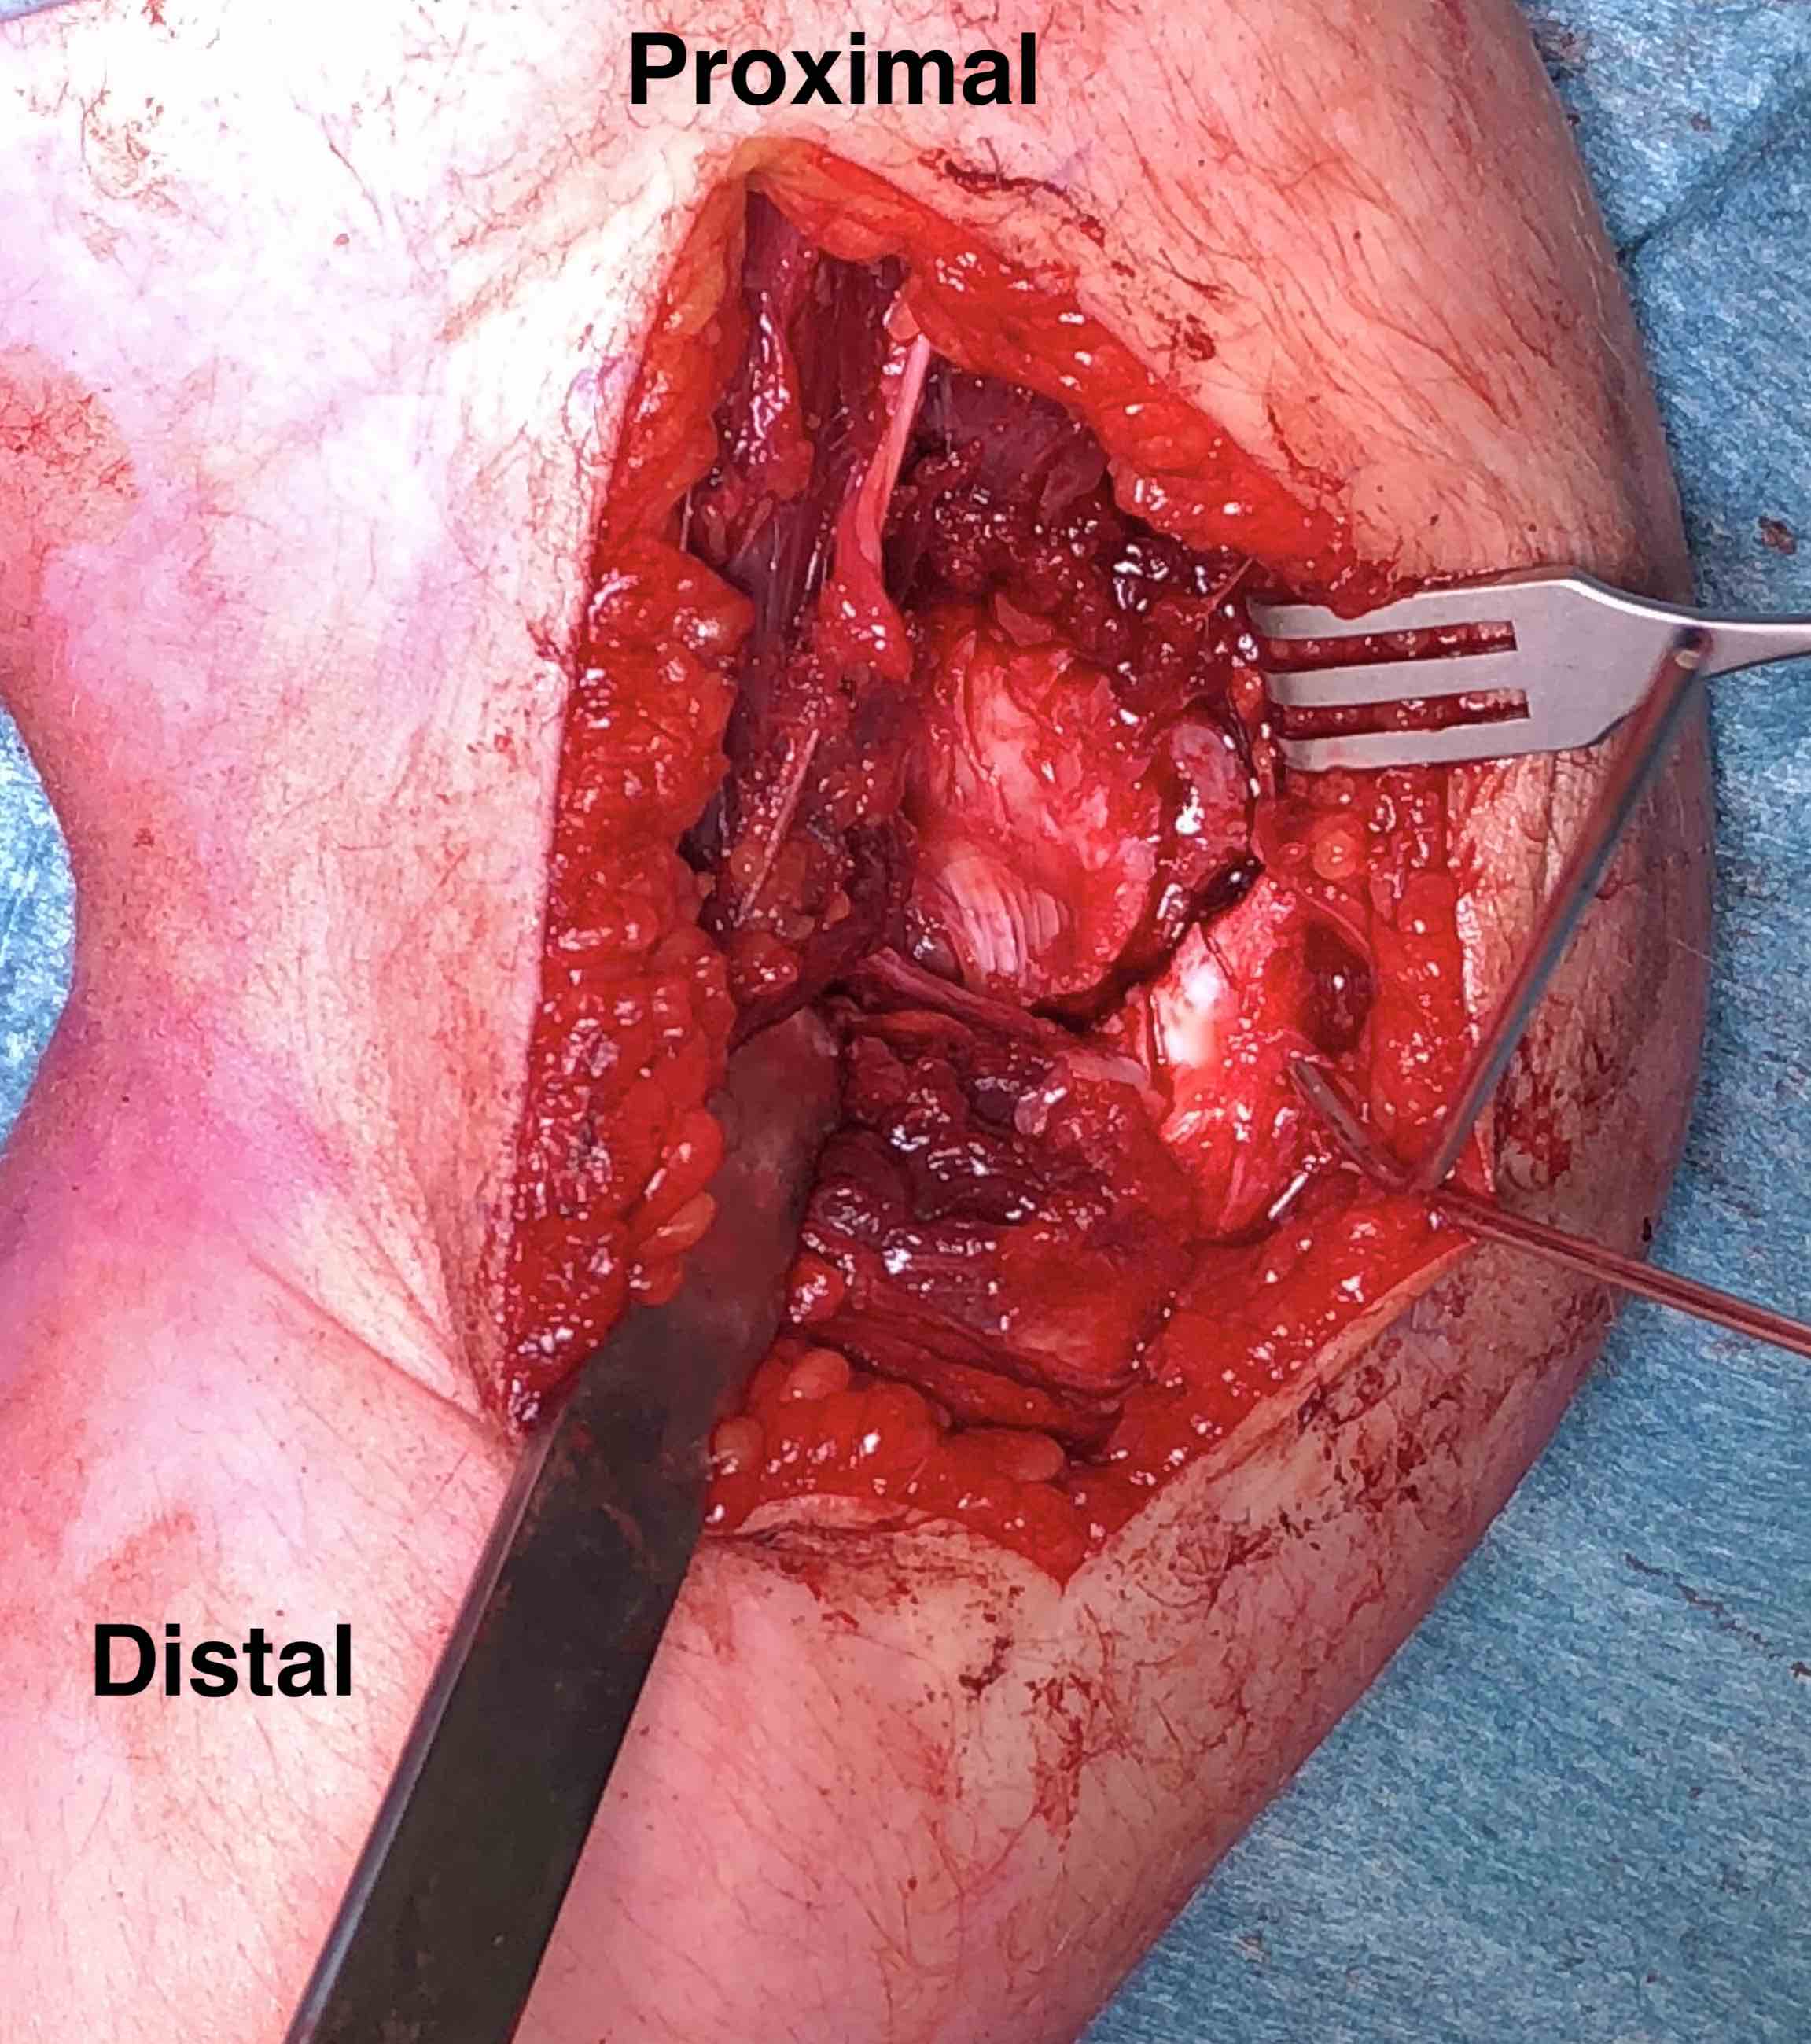

Lateral approach to distal humerus

- curved incision over lateral supracondylar ridge of humerus, and over proximal radius

- proximally intermuscular interval between brachioradialis & triceps

- proximally elevate brachioradialis and ECRL off the distal humerus

- distally split common extensor origin between ECRB and EDC and elevate anteriorly

Don't dissect posteriorly to protect blood supply

Don't need to dissect distal fragment

Use anterior homan retractor across distal humerus to elevate anterior capsule

- visualize distal joint line and perform anatomical reduction under vision

- one K wire parallel to joint surface across fracture into trochlea

- one K wire at 45 degrees to first engaging medial metaphysis

- bury K wires as need to be in for 6 weeks

Open reduction of displaced lateral condyle in left elbow